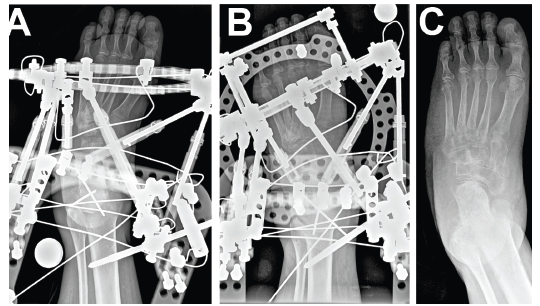

Tricortical radiographic consolidation on two orthogonal radiographs mark achievement of bony consolidation. Computed tomography may be necessary to confirm complete osseous healing in foot and ankle cases. Obtaining this endpoint then allows for removal of the external fixation.

Rate and rhythm in distraction osteogenesis significantly impacts the expression of factors involved.18 Further, several experimental studies show improved bone regeneration with continuous versus intermittent distraction osteogenesis.21 One begins distraction at a specific rate and rhythm, typically 1.0 mm a day, divided into four increments. Although this is the classically cited rate, in clinical practice, the rate can vary (0.5 mm/day to 1 mm/day in the foot and ankle) based on multiple factors including: patient age, health, medications, location and type of osteotomy.

Other reported complications include joint stiffness and subluxation, as well as osseous malalignment. During lengthening, there is a tendency for the bone segment in question to gradually veer off its intended course due to muscle forces or instability secondary to an inadequate external fixator construct.2,9,10 Other complications relate to the consolidation rate at the distraction site. Premature consolidation occurs as a direct result of an excessive latency period in which significant callus healing blocks the distraction. In contrast, prolonged or delayed consolidation can occur secondary to patient metabolic, environmental, or technical factors including: poor osteotomy technique, initial diastasis, or rapid distraction.9,10 Pin site tract infections, fracture after external fixator removal, and chronic regional pain syndrome have also been reported.19